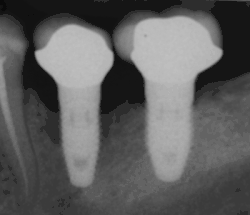

Bone loss (peri-implantitis) on implants over 7 years in a heavy smoker

Cement peri-implantitis

Dental cement under the gingiva causes peri-implantitis and implant failure.

Beyond the possibility of mechanical failure[98] which may be due to poor prosthetic fitment, wear and tear, or user-induced actions such as bruxism, dental implants are also subject to peri-implant mucositis and peri-implantitis, where gum tissue and bone mass around the implant are resorbed, and the implant gradually becomes loose, and has to be removed.[99][100] In addition, although titanium is generally well tolerated by the body, there have been cases where the build-up of titanium particles released by the implant may cause systemic inflammatory response.[101] Because there is no dental enamel on an implant, it does not fail due to cavities like natural teeth. While large-scale, long-term studies are scarce, several systematic reviews estimate the long-term (five to ten years) survival of dental implants at 93–98 percent depending on their clinical use.[15][16][17] During initial development of implant retained teeth, all crowns were attached to the teeth with screws, but more recent advancements have allowed placement of crowns on the abutments with dental cement (akin to placing a crown on a tooth). This has created the potential for cement, that escapes from under the crown during cementation to get caught in the gingiva and create a peri-implantitis (see picture below). While the complication can occur, there does not appear to be any additional peri-implantitis in cement-retained crowns compared to screw-retained crowns overall.[102] In compound implants (two stage implants), between the actual implant and the superstructure (abutment) are gaps and cavities into which bacteria can penetrate from the oral cavity. Later these bacteria will return into the adjacent tissue and can cause periimplantitis.